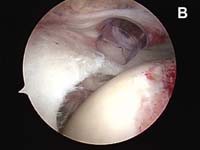

- The edge of the cuff tear must be brought back to its normal position without undue tension. This process is accomplished using techniques called mobilization or in larger tears, a technique called margin convergence. (See Fig. 4).

As tears become larger, they deform and the tendon tissue "shrinks". Thus, larger tears need to be refashioned, repaired side-to-side, or "zipped" closed using a technique called margin convergence. This technique is analogous to zippering shut an open tent flap. The rotator cuff tissue is freed from a scarred, retracted position and repaired side-to-side to ‘close the tent flap’ and restore the tissue over the top of the humeral head. (See Fig.4 and Fig.10) The repaired cuff tissue is then fixed to the site it originally tore away from using specially-designed implants called suture anchors. These are metallic or absorbable plastic devices that secure sutures to the bony attachment. The sutures are then sewn through the torn edge of the cuff to complete the repair.